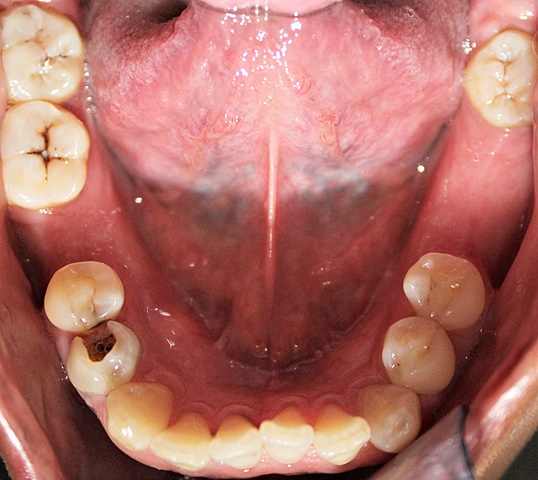

Se encontró un apiñamiento leve, restauración filtrada en OD 1.1 y 2.1. Caries en OD 1.2, 1.5 1.6, 1.7, 1.8, 2.2, 2.4, 2.5, 2.6, 2.7, 3.4, 3.5, 3.8, 4.5, 4.7 y 4.8. Ausencia de OD 3.6, 3.7 y 4.6.

Se tomó serie radiográfica periapical donde se encontró que el OD 4.4 es un diente previamente tratado donde no presenta ninguna lesión periapical y una zona radiopaca en la restauración filtrada de los OD 1.1 y 2.1.

Edentulismo Clasificación III de Kennedy inferior.

Periodontitis estadio II grado A.

Endodoncia filtrada del OD 4.4. Diagnóstico pulpar: diente previamente tratado. Diagnóstico periapical: periápice aparentemente sano

Clase de Angle:clase canina I derecha y clase canina I izquierda, ausencia de primeros molares inferiores para establecer clase molar.

Se mandó a tomar la radiografía panorámica donde se observó la posición del OD 1.8, 2.8, 3.8 y 4.8. La reabsorción osea horizontal, restauración filtrada del OD 1.1 y 2.1. El OD 4.4 previamente tratado.